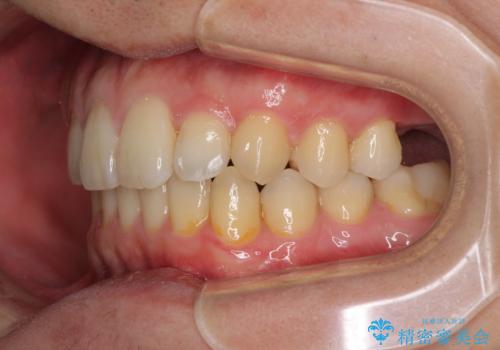

前歯のクロスバイトと抜歯が必要な奥歯の虫歯 インビザラインとインプラント治療

- 前歯のクロスバイトと、大学生のころから放置している虫歯を気にして来院された患者様です。

マウスピースでの矯正治療を希望されていましたが、前歯のクロスバイトは不十分な仕上がりや歯髄壊死などのリスクが高くなるため、術前にワイヤーで大まかに整えてからインビザラインにて矯正治療を行うこととしました。

奥歯の虫歯は抜歯が必要であったので、矯正治療前に抜歯をし、矯正治療と並行してインプラントによる補綴治療を行うこととしました。